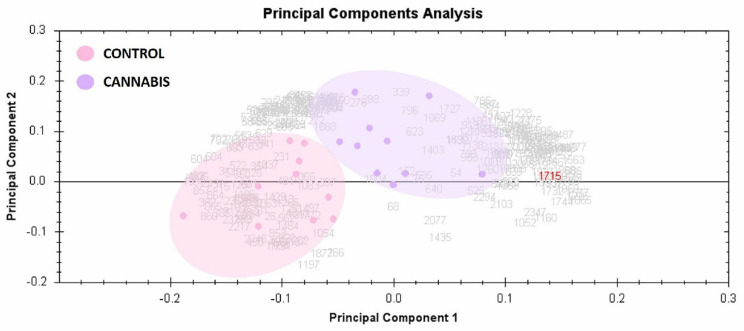

2.3. Principal Component Analysis

To determine and visualize the CUD and control subjects’ samples, the principal component analysis of the Progenesis SameSpots software was used. The analysis was made on all 121 spots that exhibited statistically significant changes in abundance identified by MS. The analysis shows that the two groups clustered distinctly based on different proteins with score of 64% (Figure 4).